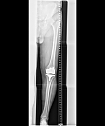

Außerdem ermöglicht die neue Röntgeneinheit die Anfertigung von Ganzbein- und Ganzwirbelsäulenaufnahmen direkt digital mit nachfolgender elektronischer fehlerfreier und versatzfreier Zusammenfügung der Bilddatensätze. Diese Ganzbein- und Ganzwirbelsäulenaufnahmen sind für die Planung endoprothetischer Versorgungen wesentlich. Darüber hinaus sind sie von großem Nutzen in der Therapieabschätzung bei Skoliose oder anderer Fehlstellungen der Wirbelsäule. Auch bezüglich der Bildqualität von im Liegen anzufertigenden Aufnahmen bietet das System wesentliche Vorteile. Häufig werden heutzutage Liegendröntgenaufnahmen mit Verwendung eines Rasters durchgeführt, um die sonst bildqualitativ beeinträchtigende Streustrahlung zu verringern. Die Röntgendosis steigt aber durch diese Rastertechnologie. Alternativ muss man die sonst schlechtere Bildqualität bei Liegendaufnahmen in Kauf nehmen, was die Befundung beeinflussen kann. Nach unserer Kenntnis erstmalig in Thüringen verfügbar, ist nun für diese schwerkranken Patienten (die deshalb nur im Liegen geröntgt werden können) das sogenannte Sky Flow Processing”, erklärt der Chefarzt.